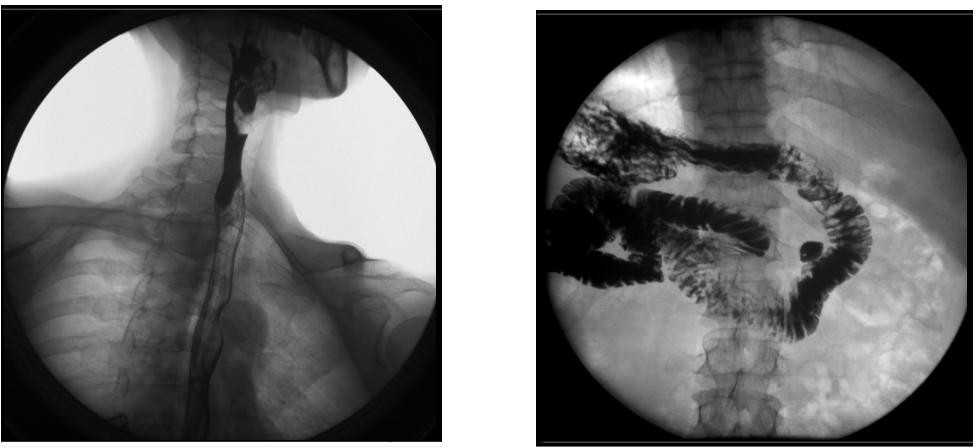

1) 胃腸數(shù)字化透視、消化道造影檢查,胸部、頭顱及全身骨骼普通攝影。

2) 胃腸、食道、脊髓、關(guān)節(jié)腔、膽道、支氣管、靜脈、周邊血管、泌尿系統(tǒng)、子宮輸卵管等數(shù)字化造影。

【臨床圖像】